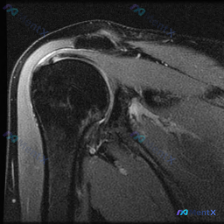

这是踝关节矢状位MRI T2序列,影像观察结果如下:

- 骨结构:胫骨远端、距骨、跟骨、舟骨、部分楔骨骨皮质轮廓完整,胫距关节间隙可见

- 关节腔:胫距关节腔内可见明显条带状T2高信号,提示大量关节积液

- 肌腱:跟腱走行连续、信号均匀,其余可见肌腱走行清晰

- 软组织:距骨后方、踝关节周围软组织可见广泛信号增高,提示水肿/炎症反应;足底筋膜及深部软组织也可见条状高信号

- 骨信号:距骨骨髓内可见边界模糊的斑片状T2高信号,提示距骨骨髓水肿

整理下来核心影像表现是胫距关节大量积液+广泛踝关节周围软组织水肿+距骨骨髓水肿三联征。